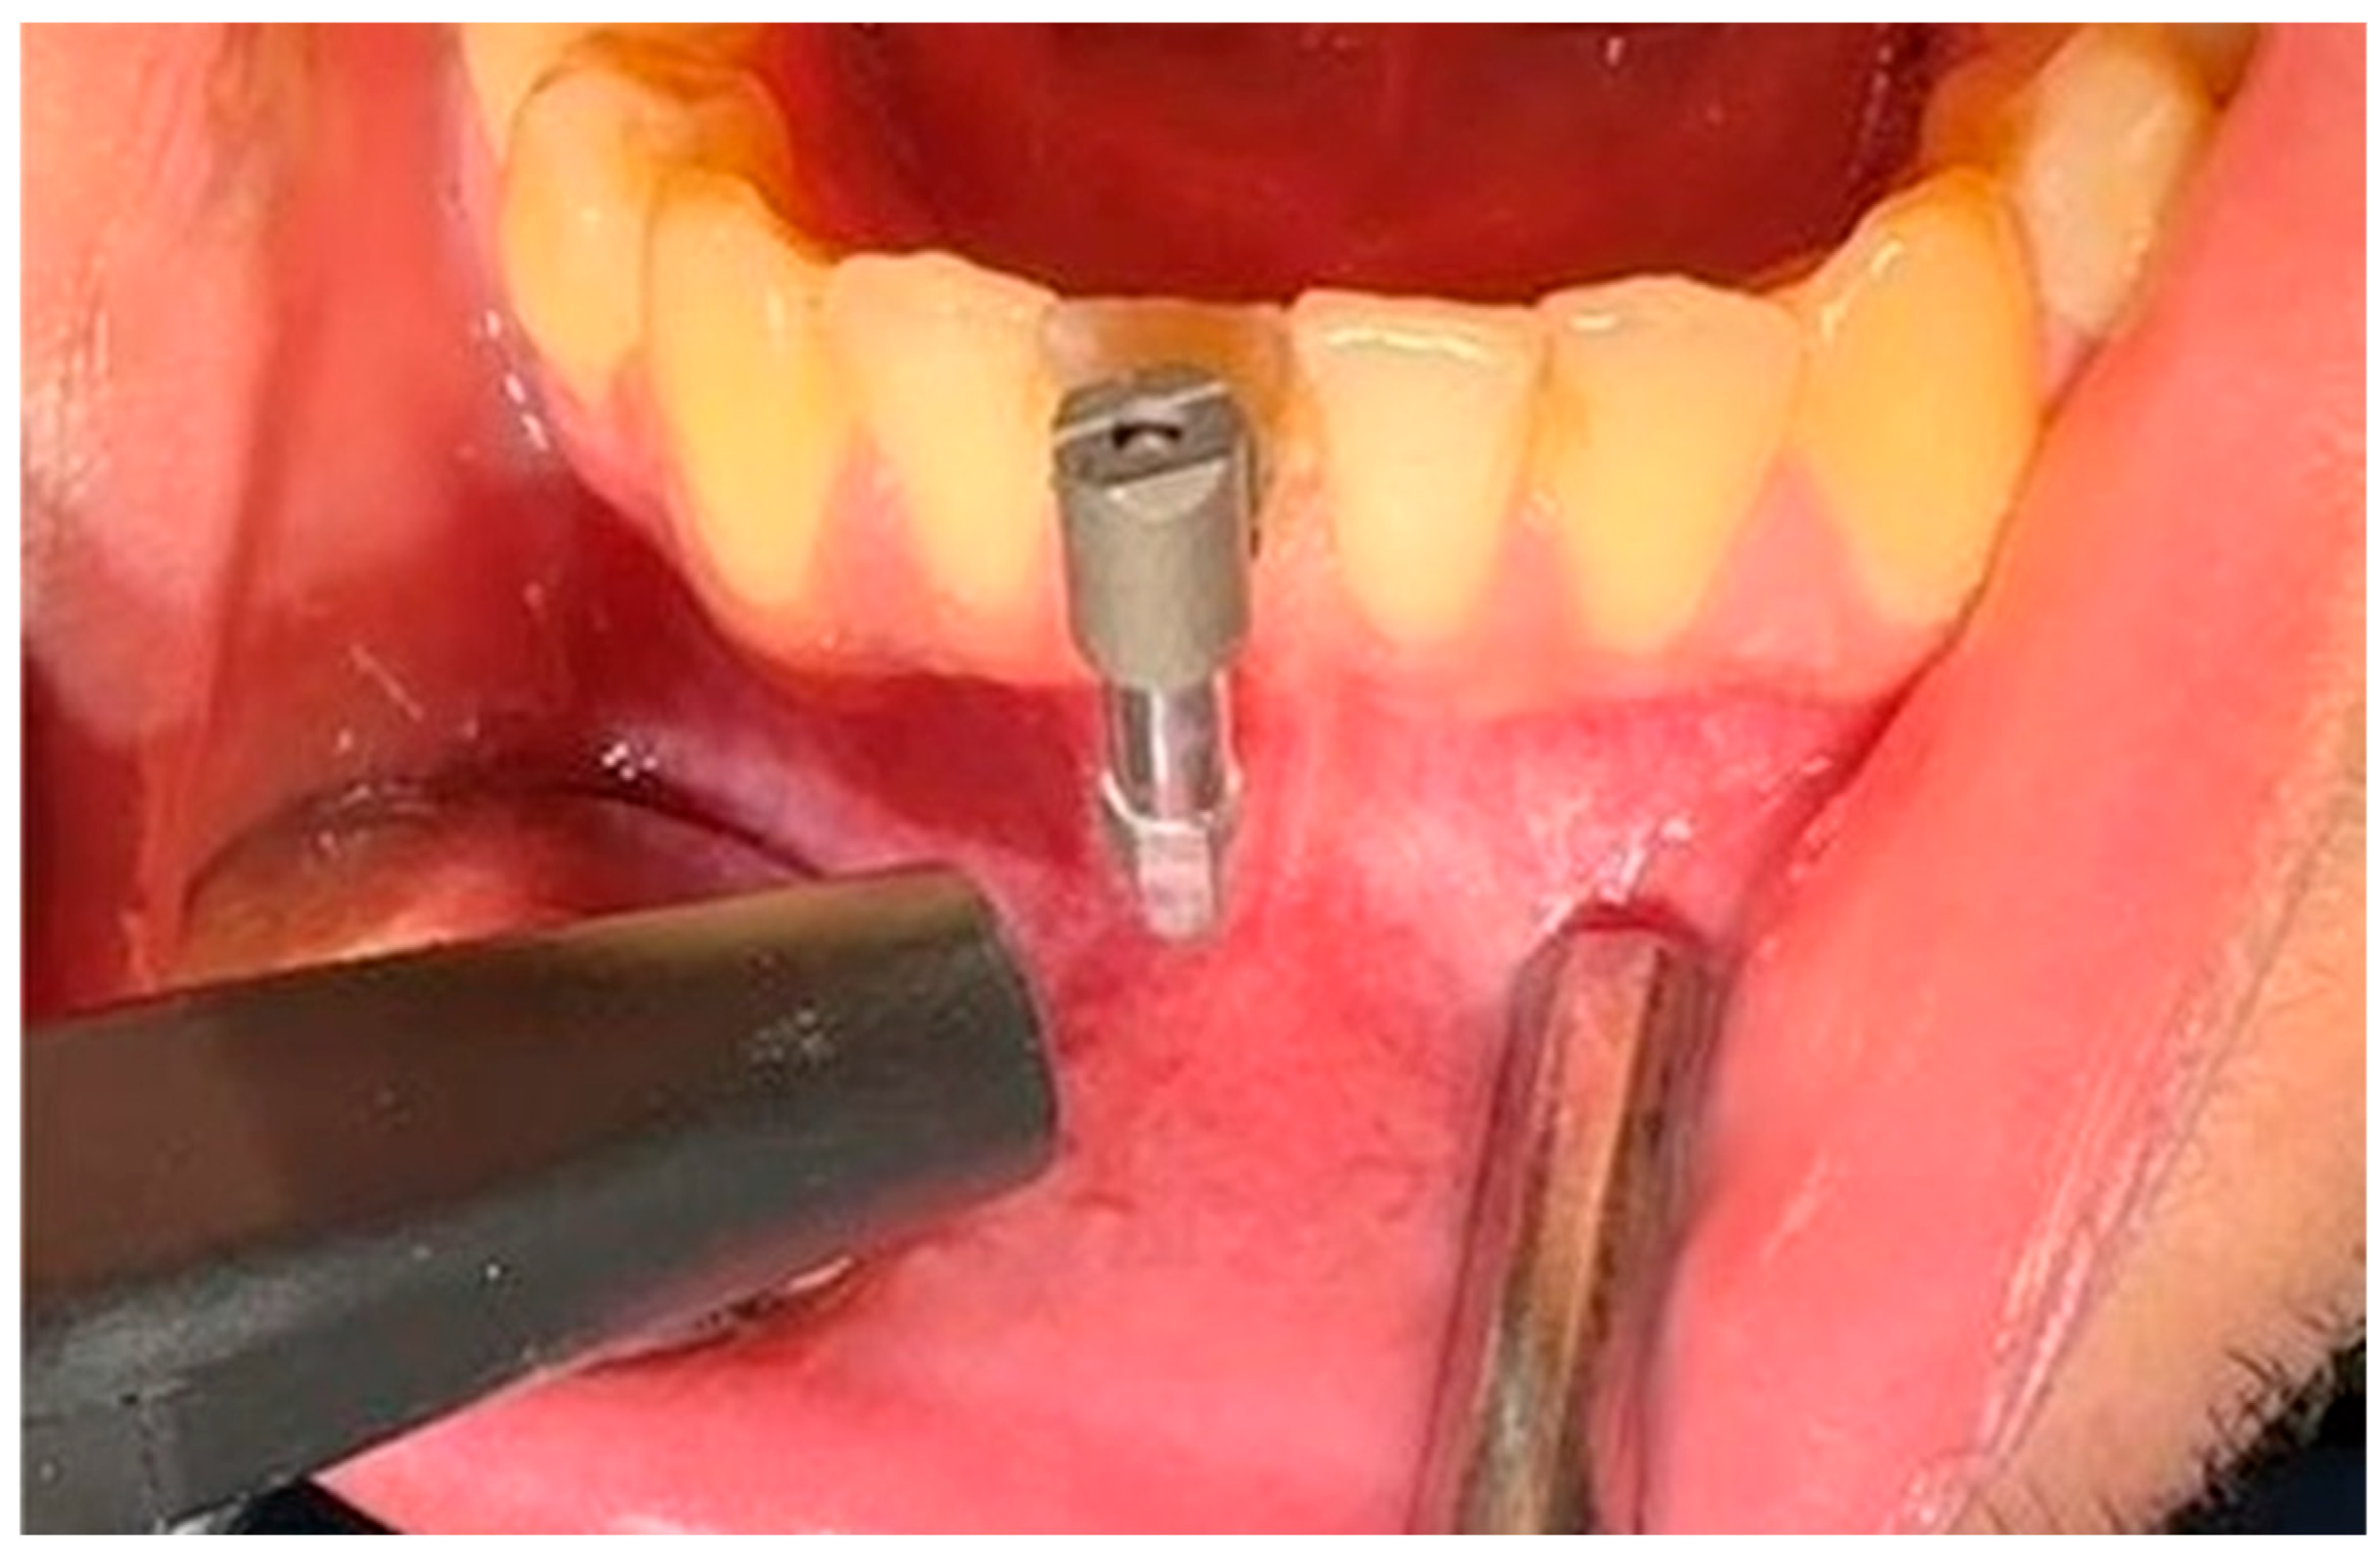

2. Materials and Methods

- Material: Medical-grade titanium, precision-machined using CNC technology.

- Design: Cylindrical base with a centrally located, threaded slot for modified SmartPeg insertion.

- Internally threaded to enable clockwise insertion of the modified SmartPeg (Figure 3b,c).

- Micro-threaded, tapered, and centered aperture.

- Diameter: approximately 1.2–1.5 mm.

- Flat base designed to conform to the buccal surface of the tooth.

- Smooth texture with micro-mechanical retention properties (Figure 3a).